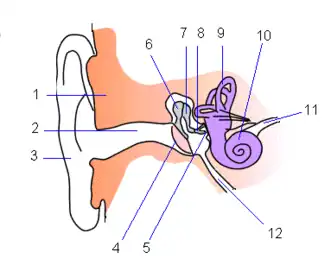

Na anatomia humana, o tímpano ou membrana timpânica, é uma membrana em forma de cone fina que separa o ouvido externo, ou conduto auditivo externo, do ouvido médio em humanos e outros tetrápodes.[1] A sua função é a de transmitir o som do ar aos ossículos na orelha média, e, em seguida, para a janela oval na cóclea cheia de fluido. Por isso, em última análise, converte e amplifica vibrações no ar à vibração no líquido. O osso martelo preenche a lacuna entre o tímpano e os outros ossículos.[2]

O número 4 é o tímpano. | |